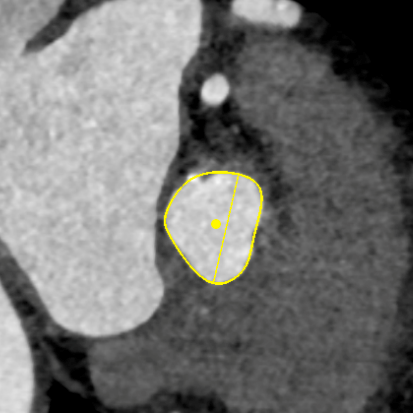

CT测量

主动脉根部CT测量

瓣环周长:68.1mm

最长直径:23.3mm

LVOT周长:69.0mm

最长直径:23.8mm

左冠开口高度:8.7mm

右冠开口高度:8.4mm